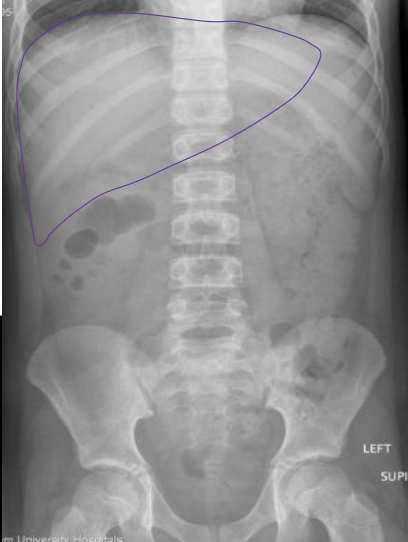

What anatomy is outlined in this image?

Liver